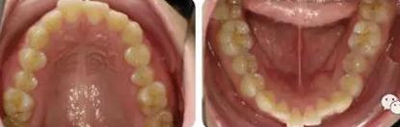

女性,24歲,主訴牙列不齊,面型突。

開唇露齒,閉口時唇肌緊張,反笑線,突面型。

上下牙列輕度擁擠,牙弓偏尖圓形;前牙深覆合深覆蓋;雙側(cè)磨牙尖牙偏遠中關(guān)系。